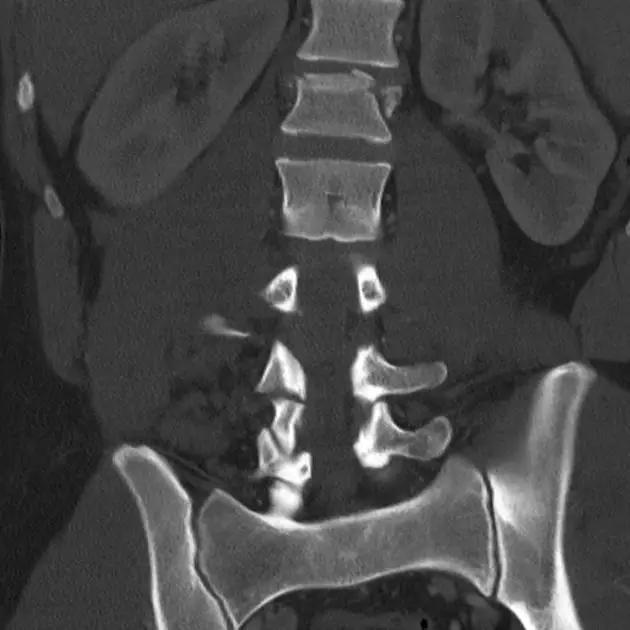

1. Burst 骨折

椎体轴向压力造成的骨折,通常发生骨折碎片向外侧的移位。可以发生在颈椎、胸椎或腰椎。

(来源:Radiopaedia)